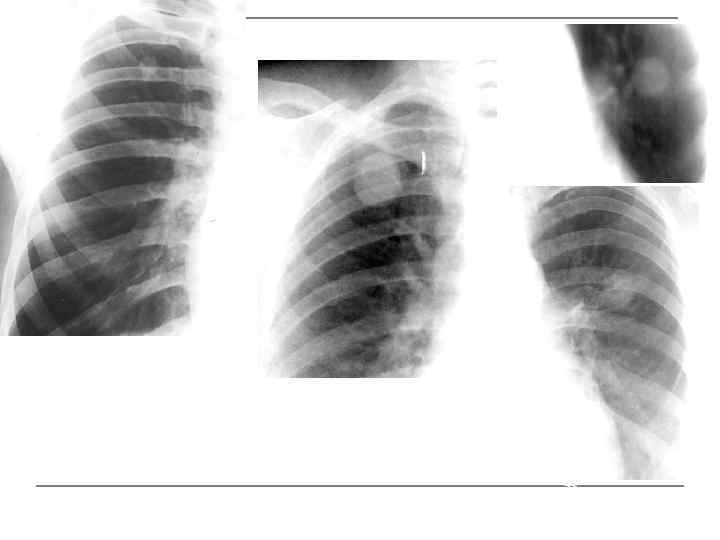

Инфильтративный туберкулез нижней доли правого легкого, фаза распада

То же наблюдение в динамике через каждый месяц